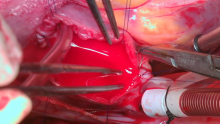

The patient underwent a median sternotomy, and cardiopulmonary bypass was initiated. A large rectangular pericardial patch was harvested and cleaned, ensuring it was positioned 1 cm from both phrenic nerves to preserve them. An aortic cross-clamp was applied, and a small right atrial (RA) incision, as described, was made. The heart was arrested using antegrade cold crystalloid cardioplegia.

The intracardiac anatomy was then examined. The interatrial septum was completely excised, followed by re-endothelialization, and a slit opening of the coronary sinus (CS).

Stay stitches were placed, as shown in the diagram in the video. The lower border of the inferior channel was approached in front of the left pulmonary veins, separating them from the left atrial appendage and mitral valve. This line continued until it reached the IVC. The upper border was then stitched, separating both the mitral and tricuspid valves until it fully incorporated the IVC and the surrounding area.